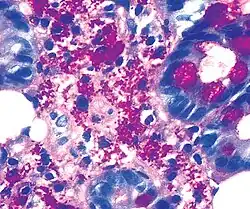

Coloration PAS

La coloration PAS (Periodic Acid Schiff) est une coloration utilisée en histologie pour mettre en évidence les polysaccharides (types mucopolysaccharides) présents dans certains tissus conjonctifs ainsi que dans le mucus. Elle est composée d'acide periodique et de réactif de Schiff.

En effet, l'acide periodique est un oxydant puissant capable de rompre la liaison covalente entre deux fonctions -OH d'un glucopyranose. Les deux fonctions aldéhyde créées réduisent le leucodérivé de la fuchsine basique de Schiff qui devient rose.

L'hématoxyline est utilisée comme contre-colorant pour augmenter le contraste (coloration des noyaux).

Il colore en rouge fuchsia les aldéhydes (sucres ou polysaccharides) de la membrane plasmique ou des acides nucléiques. Le glycogène et les glycoprotéines apparaissent roses. Ces groupements glycols apparaissent dans la membrane basale (située par exemple à l'interface entre l'épithélium et le tissu conjonctif).